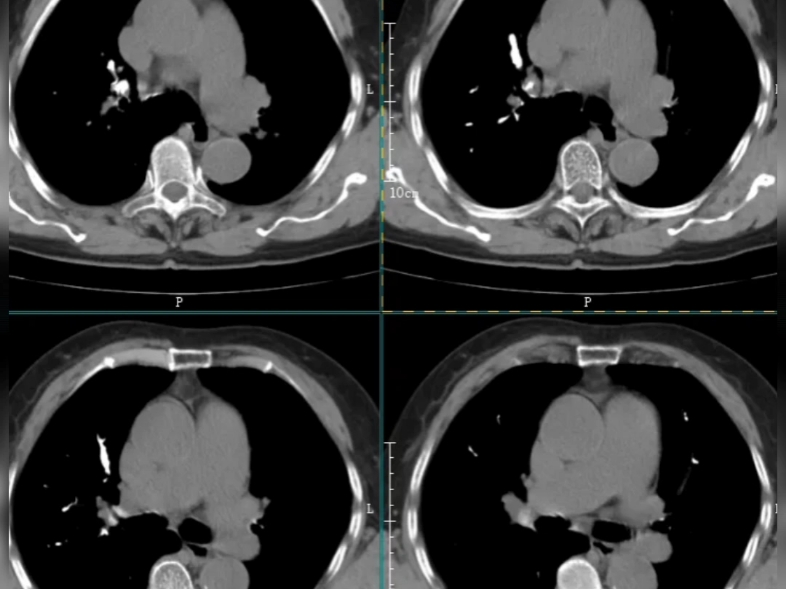

3、肺部钙化灶一般不严重以下是关于肺部钙化灶的详细解答良性状况肺内有钙化灶,临床上通常认为是良性状况或一种相对乐观的情况无影响大多数情况下,肺部钙化灶对身体没有影响,不需要过分担心或进行特殊干预常见原因肺部慢性炎症肺部钙化灶最多见于肺部慢性炎症,如肺结核是目前最常见的原因。

4、钙化病灶区域不广,对肺功能影响小,通常不需要处理,也不会导致特别严重的危害如果大面积的钙化病灶,尤其是大面积的胸膜钙化,也可以导致不同程度的现行通气功能障碍临床大多数情况下的钙化灶都是局灶性,因此不属于严重的疾病,仅仅是以往感染结核杆菌导致肺结核留下来的陈旧病灶。

5、肺部结节钙化灶一般不严重以下是具体分析形成原因肺部结节钙化通常是长时间慢性炎症刺激导致组织增生和钙盐逐渐沉积的结果处理建议肺部结节如果出现钙化,一般不需要过度担心,建议随访观察常见钙化类型错构瘤结节钙化常呈爆米花样肺结核肺部钙化最为常见,但钙化通常不规则没有固定形状。

9、大量的二氧化硅在肺部沉积后,可以形成钙化病灶肺结核经过规范化治疗后,在肺部形成增殖纤维索条钙化等多形性病灶,钙化灶最为常见常见于肺结核本身的病灶吸收,以及肺门淋巴结发生钙化,此时并不严重,没有临床症状,不影响肺功能影像学钙化灶可以长期存在,不容易消失,动态随访就可以所以,肺钙化灶表示陈旧性改变,没有特殊临床意义,不需要特殊治疗,只需要动态随访就可以,本身。

13、1 形成原因 右肺上叶钙化灶通常是肺结核治愈后留下的陈旧病灶在肺结核感染过程中,局部会有钙盐沉积,从而形成钙化灶2 病灶影响 钙化病灶区域一般比较小,对机体不会产生非常严重的影响,也不会导致明显的临床症状3 处理方式 右肺上叶钙化灶既不属于严重病灶,也不属于特殊需要处理的。

14、可能伴随终生,但通常不会引起任何症状良性病变的预示医生看到钙化灶通常会放心一半,因为钙化灶很多预示是良性病变相反,非钙化的增殖样病变可能会更令人担心,可能是一种活动性炎性或恶性病变特殊情况除非钙化灶特别大特别多,压迫了正常的肺组织,否则散在的钙化灶通常不严重综上所述。

15、肺部点状钙化灶不严重以下是关于肺部点状钙化灶的几点详细说明良性病变肺部点状钙化灶是良性的,只代表曾经的病变,对身体没有实质性影响无需治疗由于钙化灶是陈旧性病变,不会对身体造成危害,因此无需进行特殊治疗常见原因肺部钙化灶最常见的原因是肺结核病造成它是一种肺实质肺细胞。